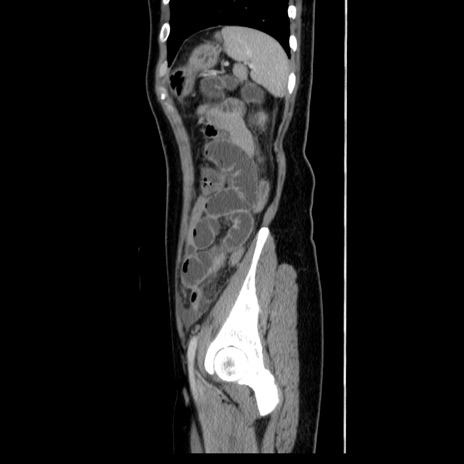

症例39(矢状断像)

【症例】40歳代女性

【主訴】上下腹部痛

【現病歴】2日目から下腹部痛あり。夜間は痛みで眠れなかった。昨日より上腹部痛と下痢が出現。臥位で痛みは軽快したため、休んでいた。本日になって臥位でも立位でも痛みが強くなってきたため救急要請。

【既往歴】子宮内膜症

【身体所見】部:平坦・軟、左上下腹部に圧痛あり、反跳痛あり。

【データ】WBC 21800、CRP 26.78

CT